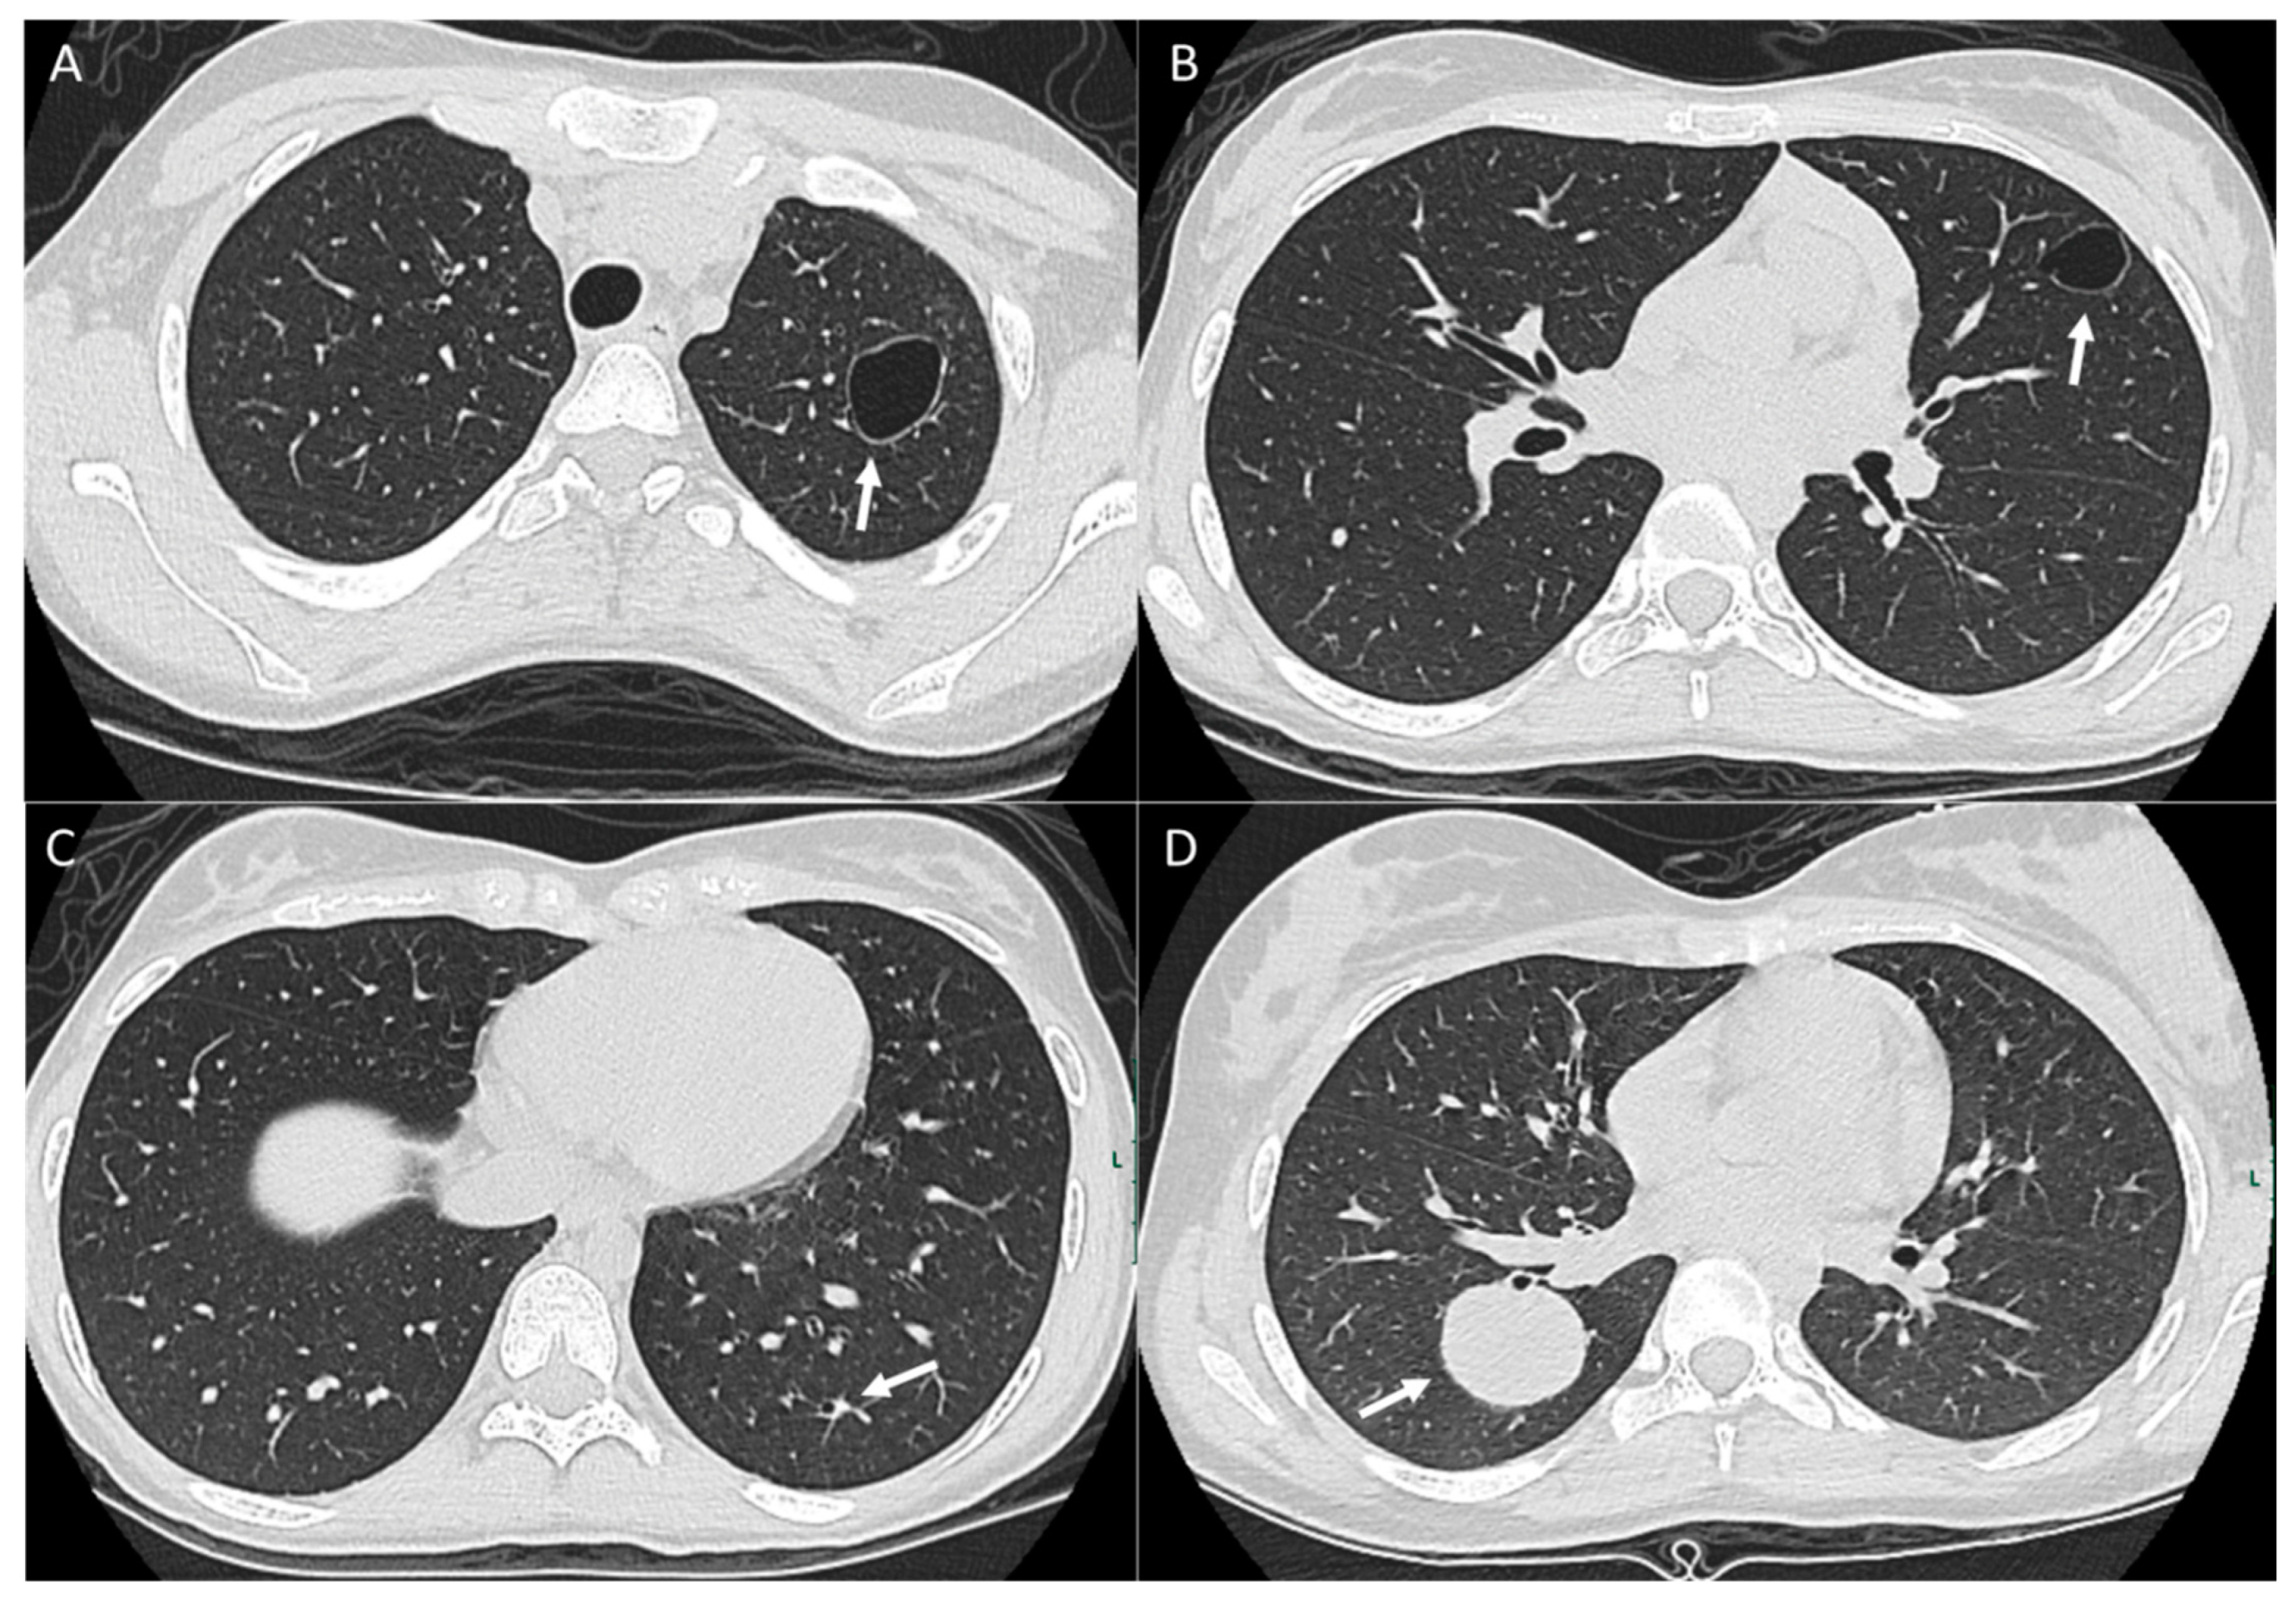

2.1. Parenchymal Metastasis

2.5. Management